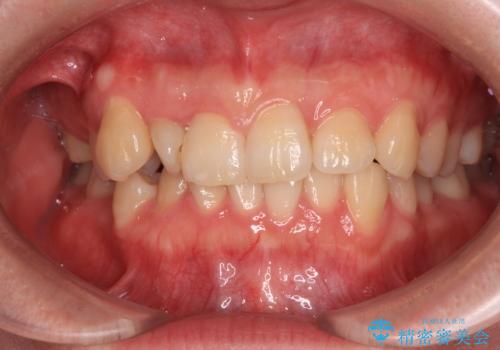

捻転の強い前歯 ワイヤー装置での非抜歯矯正